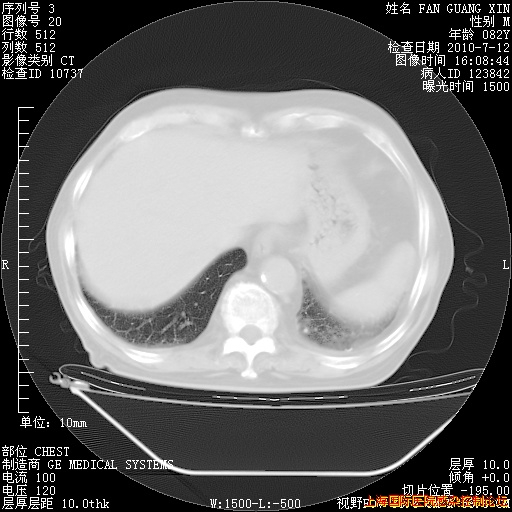

6月12日纵膈窗

今天复查CT

今天CT

整整相隔30天的肺部CT好像有所好转啊。甲强龙减量第3天,需要观察体温。